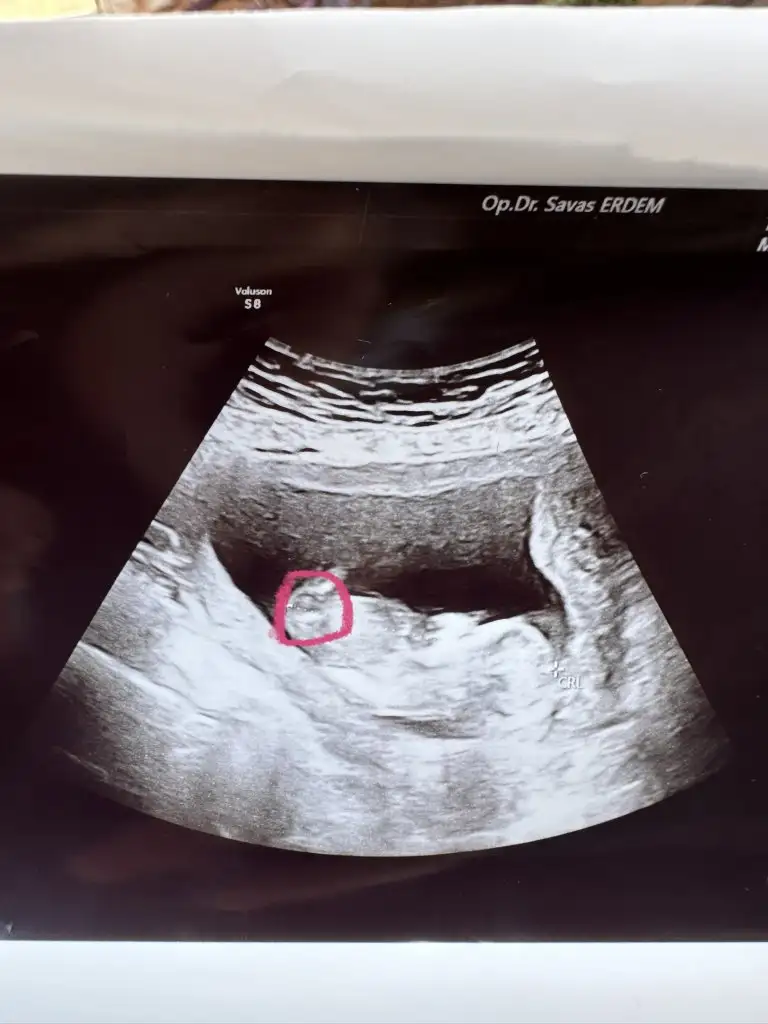

Nub teoriye göre bakarmisniz?

Bu resm

Eklentiler

• 16968682069364493656588897443361.webp

40,4 KB · Görüntüleme: 65